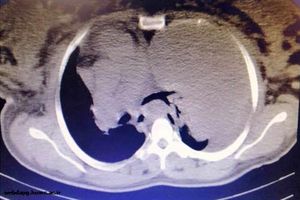

تومور 2 کیلویی با موفقیت از ریه سمت چپ یک زن باردار هرمزگانی در بیمارستان شهید محمدی بندرعباس خارج شد.